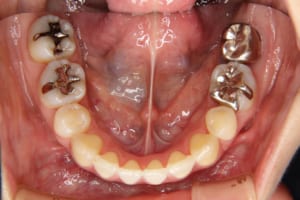

上下顎前突を伴う叢生の医療関係者の方の治療例

治療前

| 主訴 | 上の前歯が出ている |

| 治療内容 | リンガルブラケット(舌側矯正/裏側矯正)を使用した成人矯正治療を行いました。 |

| 使用した装置 | リンガルブラケット 歯科矯正用アンカースクリュー(2本) 筋機能訓練(MFT)は行っていません |

| 抜歯および非抜歯 | 上の左右第一小臼歯、右側第三大臼歯(親知らず) 下の左側第二小臼歯、右側第一小臼歯、左右第三大臼歯(親知らず) |